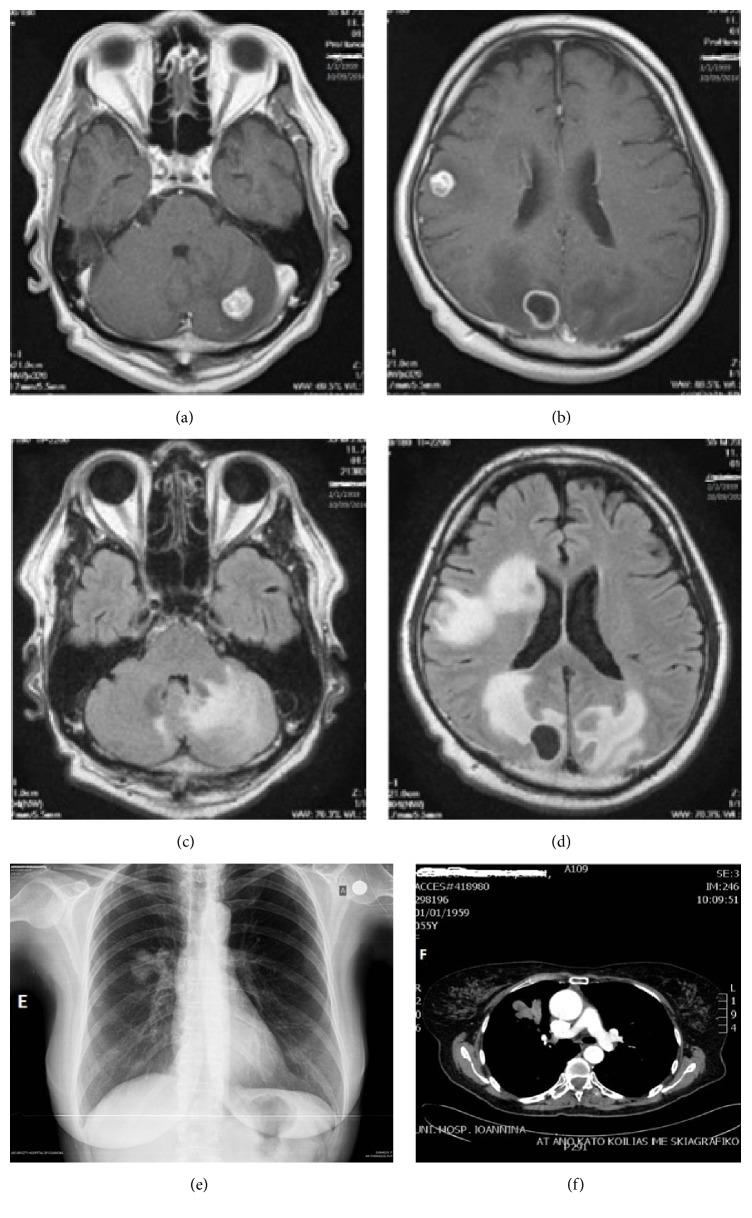

Malignant melanoma involving the respiratory tract is nearly always metastatic in origin, and primary tumors are extremely rare. Published data on primary pulmonary malignant melanomas are limited. Up to now 40 relevant cases have been reported in the English literature. Herein, we report a case of a 56-year-old female patient who presented with intracranial metastases due to primary pulmonary melanoma. She underwent bronchoscopy and died 5 months after the initial diagnosis despite the administered biochemotherapy and subsequent immunotherapy. To establish the diagnosis of primary pulmonary malignant melanoma, any extrapulmonary origin was excluded by detailed examination and radiographic imaging. Moreover, an extensive review of the literature regarding this rare entity has been performed.

累及呼吸道的恶性黑色素瘤几乎总是转移性的,原发性肿瘤极为罕见。关于原发性肺恶性黑色素瘤的已发表数据有限。截至目前,英文文献中已报道了40例相关病例。在此,我们报告一例56岁女性患者,因原发性肺黑色素瘤出现颅内转移。她接受了支气管镜检查,尽管接受了生物化疗及随后的免疫治疗,但在初次诊断后5个月死亡。为确立原发性肺恶性黑色素瘤的诊断,通过详细检查和影像学检查排除了任何肺外起源。此外,还对关于这一罕见实体的文献进行了广泛回顾。